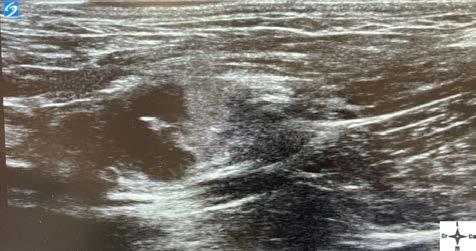

Diagnóstico por imagen Los hallazgos no son específicos de pacientes infecta dos con parvovirus. Las radiografías abdominales pue den ser normales al inicio de la enfermedad, o mostrar signos de íleo con distensión de asas intestinales por acúmulo de líquido o gas. Los signos ecográficos son asimismo inespecíficos, mostrando áreas de distensión con fluido y gas tanto en estómago como en intestino, íleo con movimientos peristálticos inefectivos, efusión peritoneal anecoica, etc.1,2,5,6 Ambas técnicas ayudan a descartar otras causas del cuadro clínico, como son cuer pos extraños, obstrucción e invaginación intestinal.1,2,5,6

Figura 3. Medición de la presión arterial no invasiva mediante un méto do oscilométrico en un paciente canino con parvovirus. Figura 4. Medidas de bioseguridad para evitar la propagación intra hospitalaria del parvovirus: uso de bata, guantes, calzas y material ex clusivo para estos pacientes. Figura 5. Infección del punto de inyección por catéter intravenoso, con necrosis de la piel y presencia de contenido purulento, en un paciente canino leucopénico por parvovirus. Figura 6. Radiografía de tórax laterolateral de un paciente canino tras la inserción de un catéter venoso central para comprobación de la co rrecta colocación (vena cava craneal).